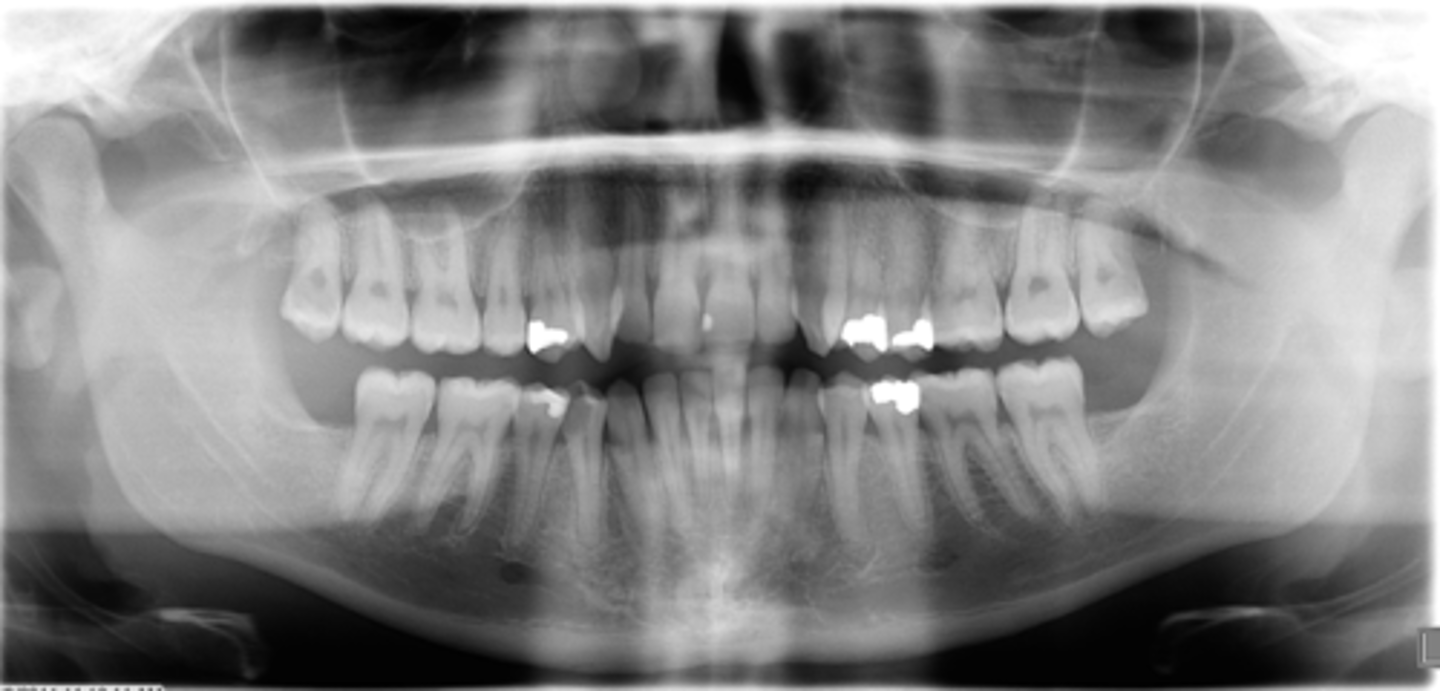

ID the positional error from the radiograph:

None - ideal